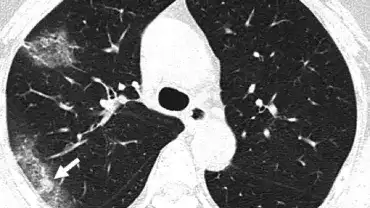

Z najnowszej analizy chińskich lekarzy nad wpływem koronawirusa SARS-CoV-2 na wątrobę, wynika, że może on ją poważnie uszkadzać, nawet u osób, które przechodzą chorobę COVID-19 bezobjawowo, z czego wynika, że infekcja stanowi potencjalne zagrożenie… Czytaj więcejWirus SARS-CoV-2 może nieodwracalnie uszkadzać płuca

Lekarze z Chińskiego Uniwersytetu Naukowo-Technicznego w Wuhan dowiedli, że nowy koronawirus SARS-CoV-2 może powodować trwałe, nieodwracalne uszkodzenia płuc. Naukowcy przebadali zwłoki ofiar choroby COVID-19, a wyniki autopsji opublikowano na… Czytaj więcejCo jeść i pić, aby wzmocnić naturalną odporność organizmu na infekcje?